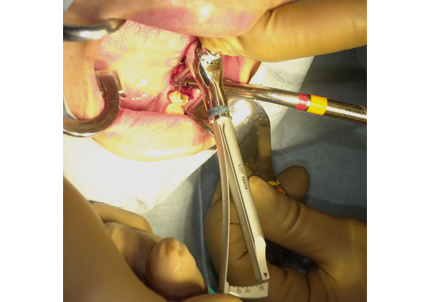

3. 右上1番・左上2番 SST(ソケットシールドテクニック)

【右上1番SST 口蓋側歯根の抜歯】

【左上2番 SST 口蓋側歯根の抜歯】

4. 右上2番インプラント埋入

埋入後に初期固定35N/cmを確認する